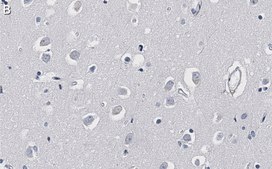

Immunohistochemistry (Paraffin) Analysis: A 1:1,000 dilution from a representative lot detected -Synuclein in human cerebral cortex and rat cerebellum tissue sections.